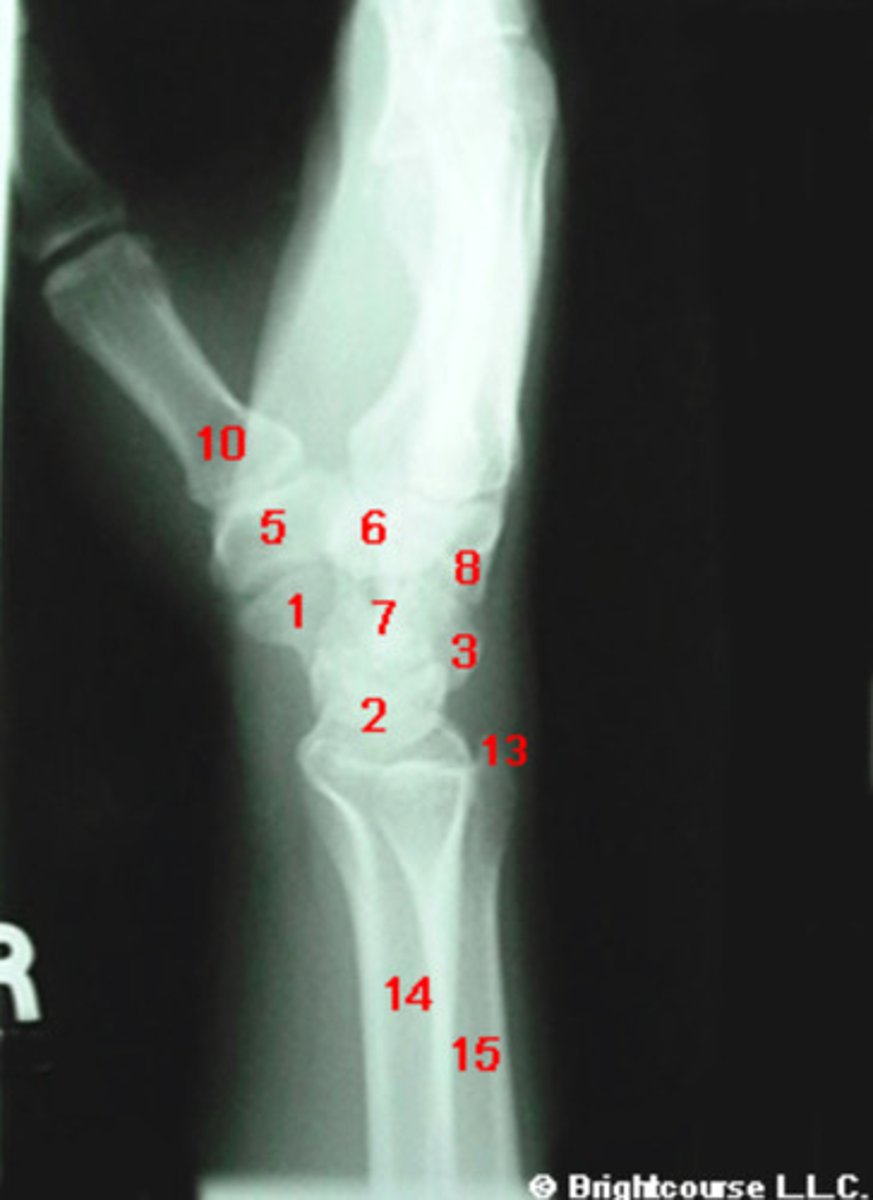

What structure is indicated by number 1?

What structure is indicated by number 2?

What structure is indicated by number 3?

What structure is indicated by number 4?

What structure is indicated by number 5?

What structure is indicated by number 6?

What structure is indicated by number 13?

What structure is indicated by number 12?

What structure is indicated by number 10?